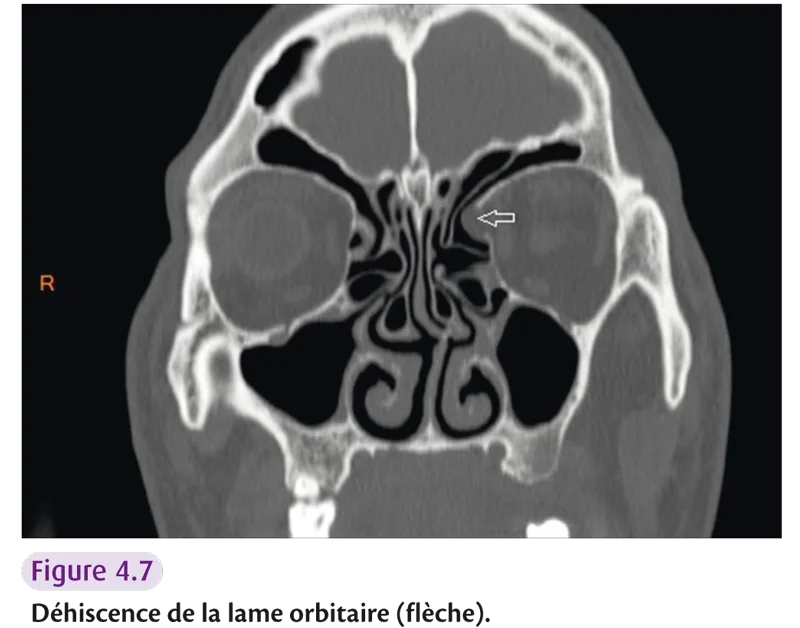

Risque de plaie orbitaire : – déhiscence de la lame orbitaire (figure 4.7) ; – hypoplasie du sinus maxillaire ; – processus unciné atélectasique.

Fig 4.7